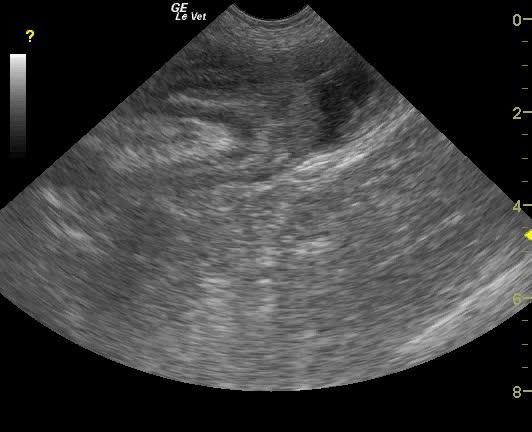

The distal small intestine in this patient presented an obstructive pattern with dilated small intestine followed by what appeared to be ileocecocolic intussusception. This was confirmed in long and short axis. Some hyperechoic reactive fat was present within the intussusception itself as well as associated with the serosa.